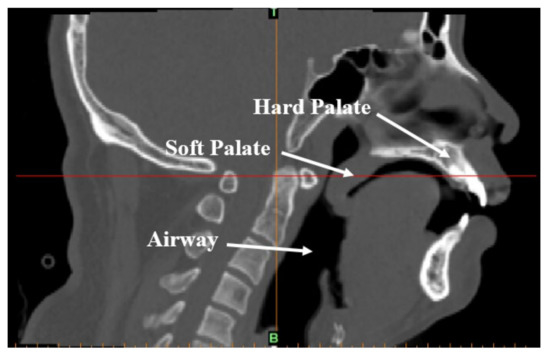

Figure 2.

CT-scanned image of the upper airway of an OSAHS patient in a supine position and sleeping naturally.